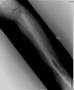

Immediate exchange nailing to unreamed nail four month later by retrograde route

Complete union of bone and fused ankle